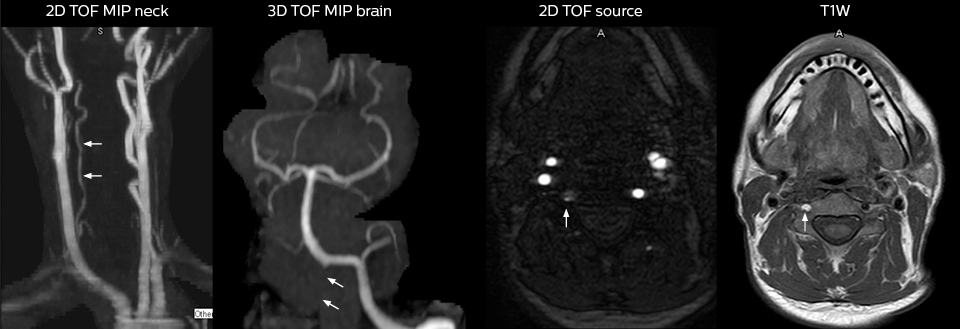

Pour minimiser la durée des acquisitions, des protocoles d’examen IRM rapides (ExamCards) ont été mis au point. Ils réduisent la durée d’acquisition totale à moins de 10 minutes pour certains examens. Des techniques comme le mDIXON (DIXON modifié) sont utilisées pour une acquisition solide des images d’IRM sans graisse dans l’environnement stressant des urgences.

Pour le Dr Karis, le prochain objectif du service d’urgences neurologiques est de passer de la TDM à l’IRM pour les patients souffrant d’un AVC ou d’un AIT, l’occasion d’offrir à ces patients une prise en charge alternative. Par ailleurs, les urgences collaborent actuellement avec les autres services de façon à encourager la réalisation d’examens ciblés avec leur matériel d’IRM. Ces améliorations dans le processus de travail et le diagnostic plus rapide des patients permettront de réduire davantage la durée d’acquisition.

2. Grimm JM, Schindler A, Schwarz F, Cyran CC, Bayer-Karpinska A, Freilinger T, Yuan C, Linn J, Trelles M, Reiser MF, Nikolaou K, Saam T. Computed tomography angiography vs 3 T black-blood cardiovascular magnetic resonance for identification of symptomatic carotid plaques. J Cardiovasc Magn Reson. 2014;16:84.